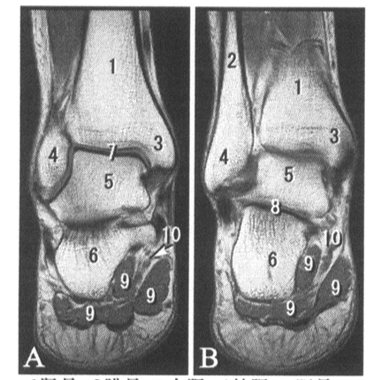

• 16.2 四肢断层解剖

读片作业

写出图中数字标注的结构名称